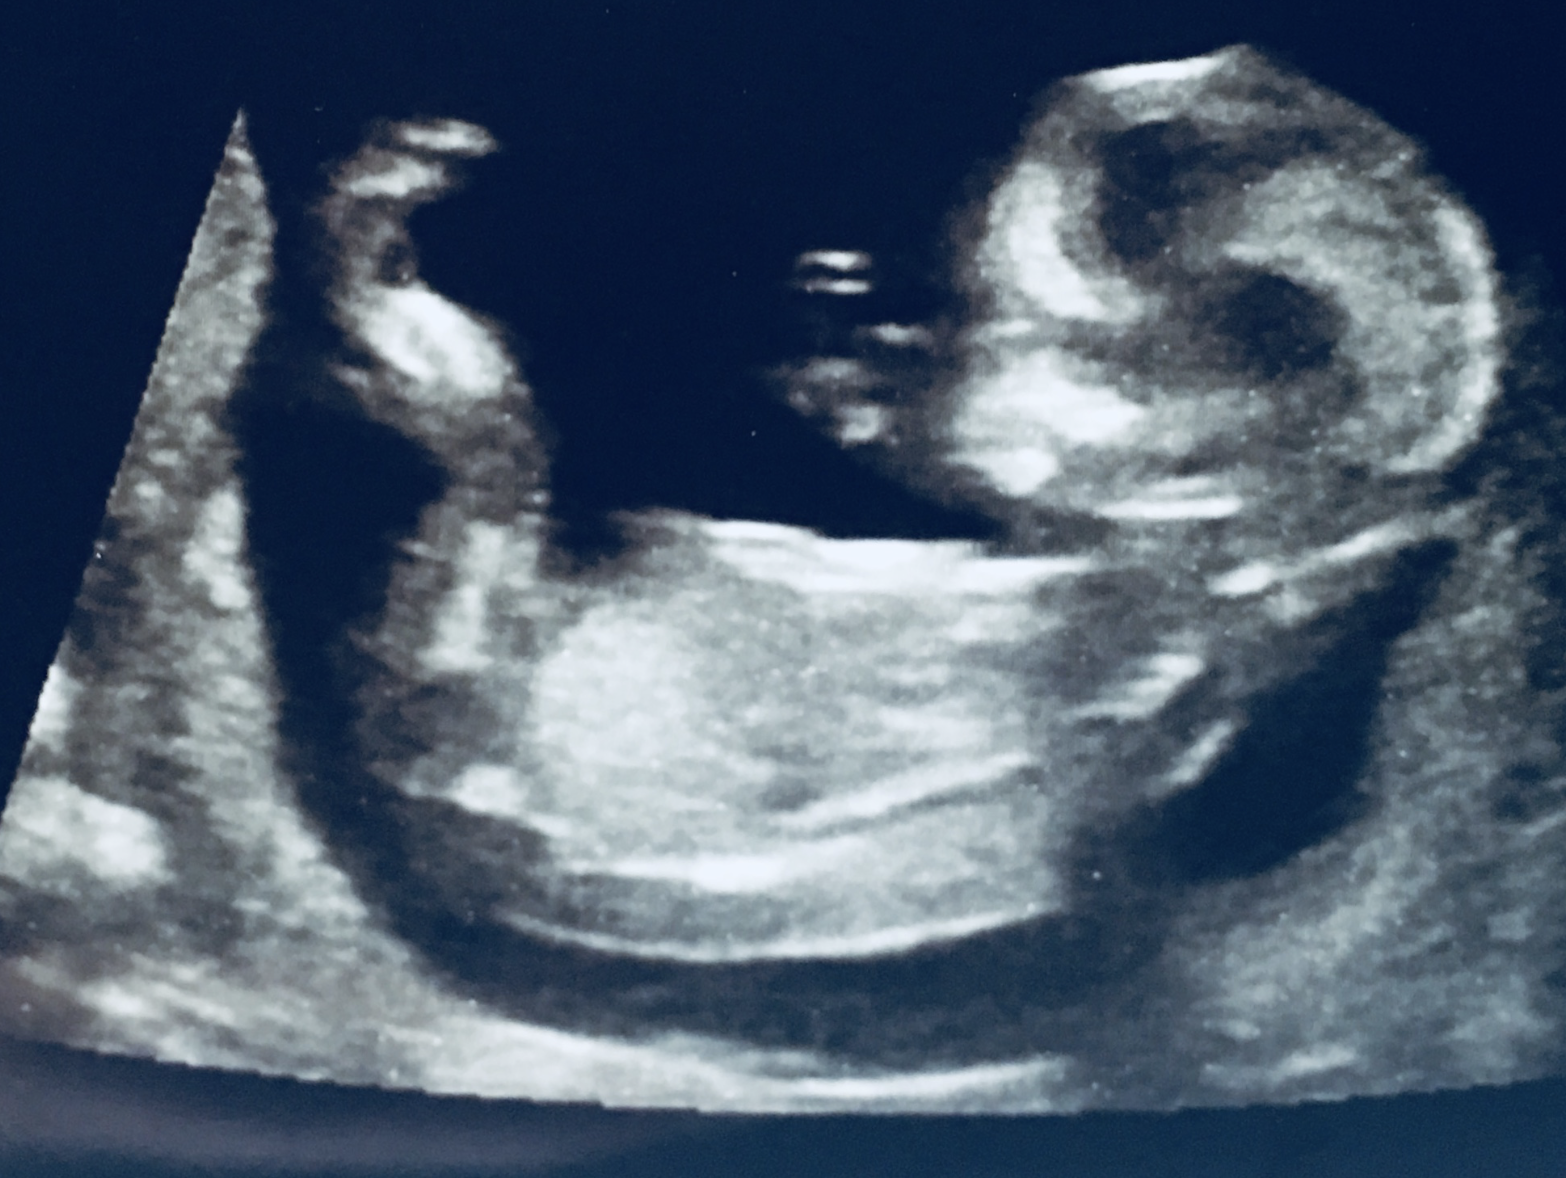

Another transvaginal ultrasound today. Everything looks great! Anyone else have an upside down babe? Last ultrasound was upside down too. By this ultrasound I'm thinking boy. Just doesn't look very girly to me!